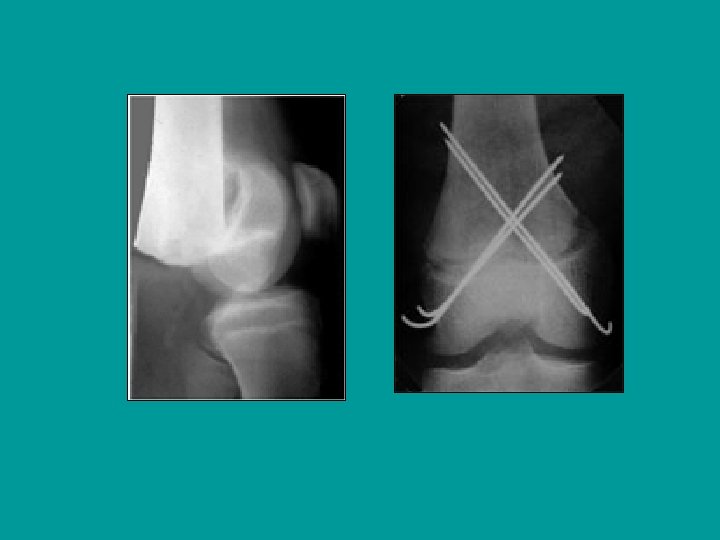

Embrochage percutané

Résultat après 5 semaines et l’ablation des broches

Salter I très déplacé : réduction et embrochage percutané